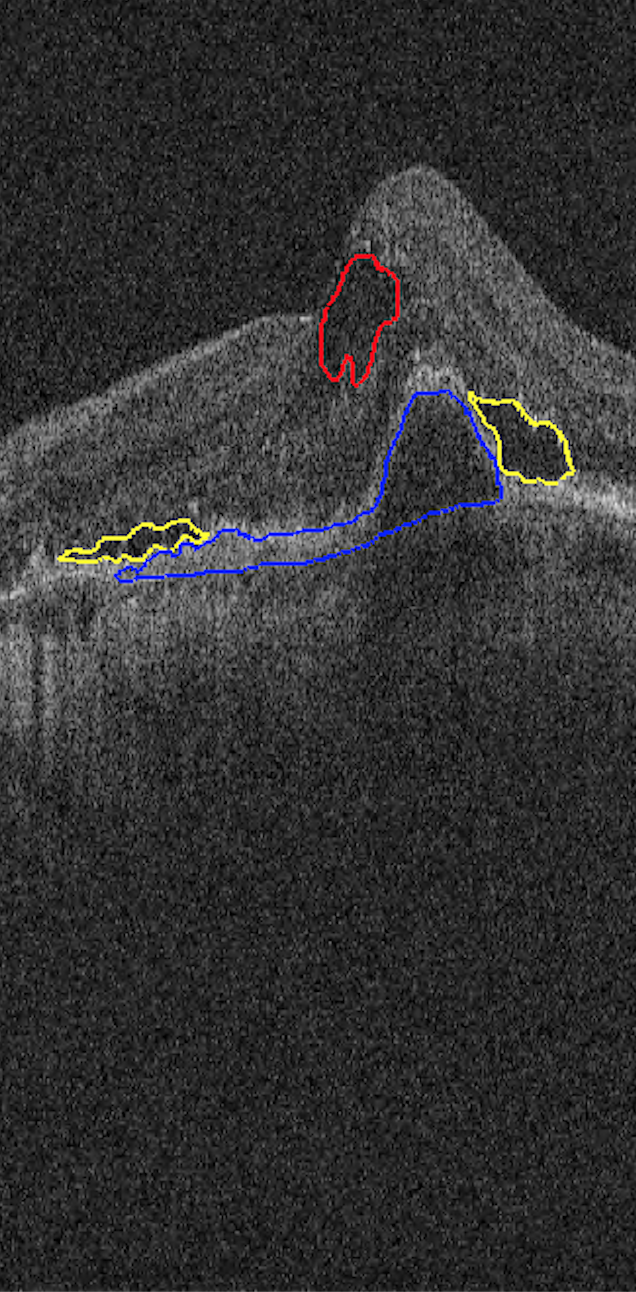

The images used in this study are provided by the MICCAI RETOUCH Group[1]. There were 3 training data sets and a total of 70 volumes, with 24 volumes acquired with each of the two OCT imaging devices: Cirrus (Zeiss) and Spectralis (Heidelberg), and 22 volumes acquired with T-1000 and T-2000 (Topcon, collectively referred to by the manufacturer name in the rest of paper). For each volume from these three devices, the numbers of B-scans were 128, 49 and 128, respectively. Three different types of fluid, namely the intraretinal fluid (IRF), subretinal fluid (SRF) and the pigment epithelial detachment (PED) were manually labeled and provided as ground truth. Although not all B-scans contained fluid, there was at least one type of fluid in each volume. Topcon images with and without macular edema are shown in Fig 1 for each commercial device.

| (a) Cirrus | (b) Spectralis | (c) Topcon |

| (3) | ||||

Both Dice and AVD were computed per volume. For each type of fluid, the segmentation was measured separately, and volumes which doesn’t contain this type of fluid were ignored for its measurement. The mean and standard deviation of AVD is presented in Table 1 and the Dice index was displayed in Fig 3. The red indicates outliers that were caused by two reasons: 1) the volume only contained a very small area of fluid and the proposed method failed to detect it, such as left panel in Fig 4; 2) the retina was warped too much, such as right panel in Fig 4 due to extremely severe disease and the proposed method could not recognize all of the fluid pixels, as there was no similar volume with which to train the network in the leave-one-out experiment.